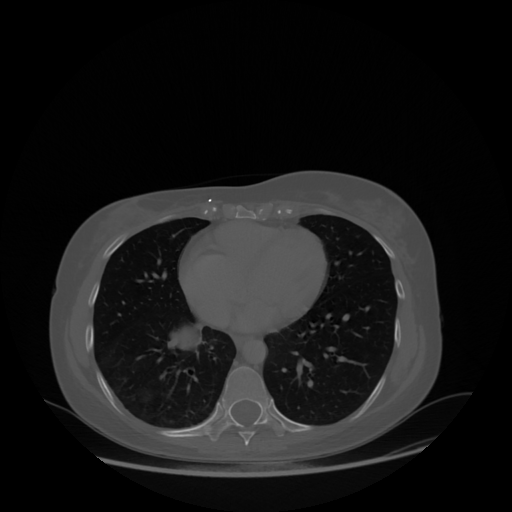

Generated VENOUS CT scan (A→B translation)

Lung window (WL -600, WW 1500 β†’ Low βˆ’1350, High +150)